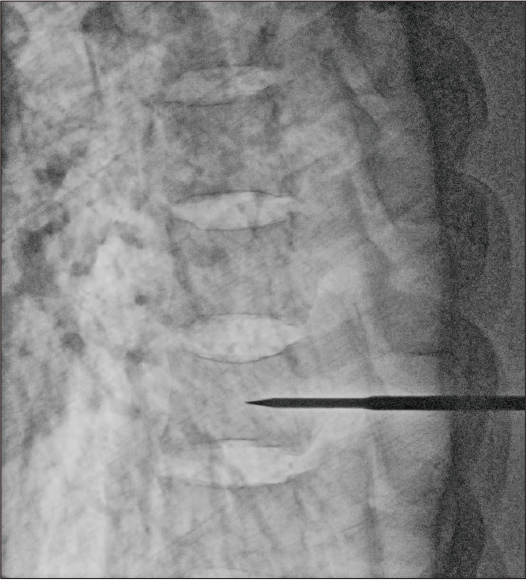

Dosis: 8,4 mA

Nach Anwendung der dynamischen Verarbeitung + Rauschunterdrückung